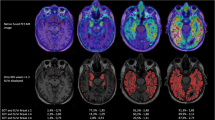

Associations between CSF p-tau and tau PET are presented in Table 2. Using all subjects CSF p-tau was associated with higher [18F]flortaucipir BPND in the entorhinal cortex (sβ = 0.46), limbic (sβ = 0.45), and neocortical region (sβ = 0.43), all p < 0.01. Within-group correlations were stronger for SCD subjects than for MCI/AD patients, with strongest correlations seen in the limbic region (sβ = 0.59, p < 0.01, Table 2, Fig. 1). Within the SCD subjects, the relationship between CSF p-tau and [18F]flortaucipir BPND was driven by the amyloid positive individuals (Fig. 1). Note that the variance of the SCD subjects patients is smaller than for MCI/AD patients, therefore a more gradual slope is observed for association between CSF p-tau and limbic, neocortical tau, although sβs are stronger for SCD. Comparable results were seen for CSF t-tau (Supplementary Table 4, Supplementary Fig. 1).

Scatterplots of the observed relationship between CSF p-tau with entorhinal, limbic, and neocortical [18F]flortaucipir BPND (top row, a–c) and SUVr (bottom row, d–f). Each symbol represents one subject. The fitted lines are stratified over AD (blue) and SCD subjects (red); closed circles are Aβ positive, open circles are Aβ negative. Correlations were adjusted for age, sex, and time lag between LP and [18F]flortaucipir PET scan

SUVr vs BPND

Although SUVr overestimated BPND values (Table 1), comparable results were obtained for SUVr and BPND. Overall, higher p-tau was related to higher entorhinal (sβ = 0.50), limbic (sβ = 0.47), and neocortical (sβ = 0.43) [18F]flortaucipir SUVr, all p < 0.01 (Table 2). In line with BPND, within groups, correlations were stronger for SCD subjects, and strongest correlations were seen in the limbic region (sβ = 0.67 p < 0.01, Table 2, Fig. 1). Voxel-wise analysis confirmed comparable associations between [18F]flortaucipir BPND or SUVr and CSF p-tau (Fig. 2), and the associations with cognition and atrophy were essentially the same for SUVr (Supplementary Tables 7, 8) and BPND (Tables 3 and 4).